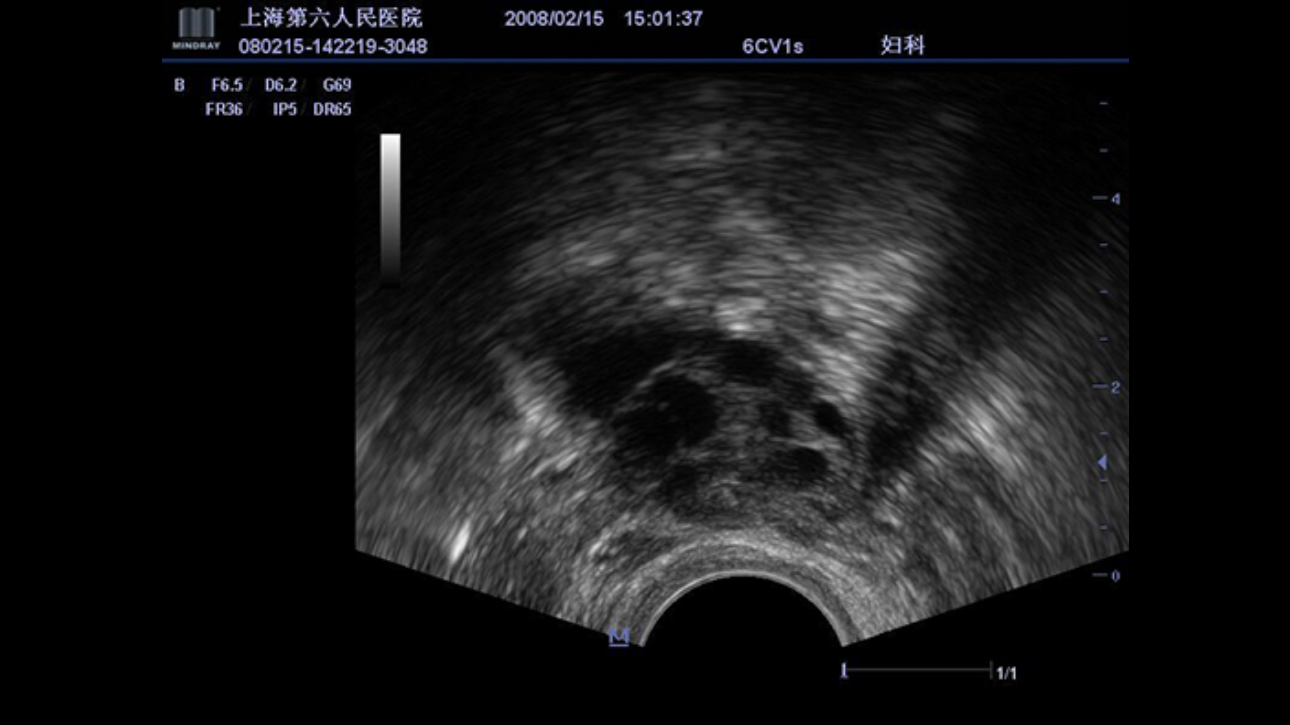

PSHITM (Phase Shift Harmonic Imaging)

Purified Harmonic Imaging for better contrast resolution providing clearer images with excellent resolution and less noise.